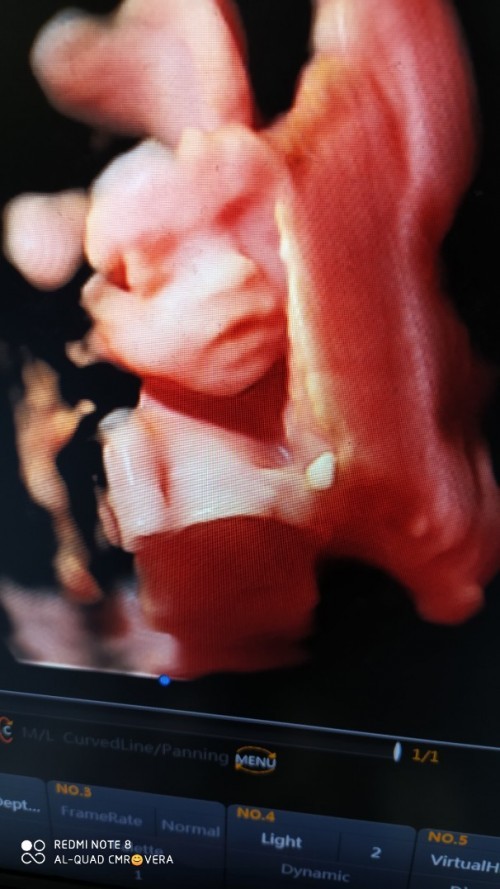

ini waktu Uk 33 w bun😅